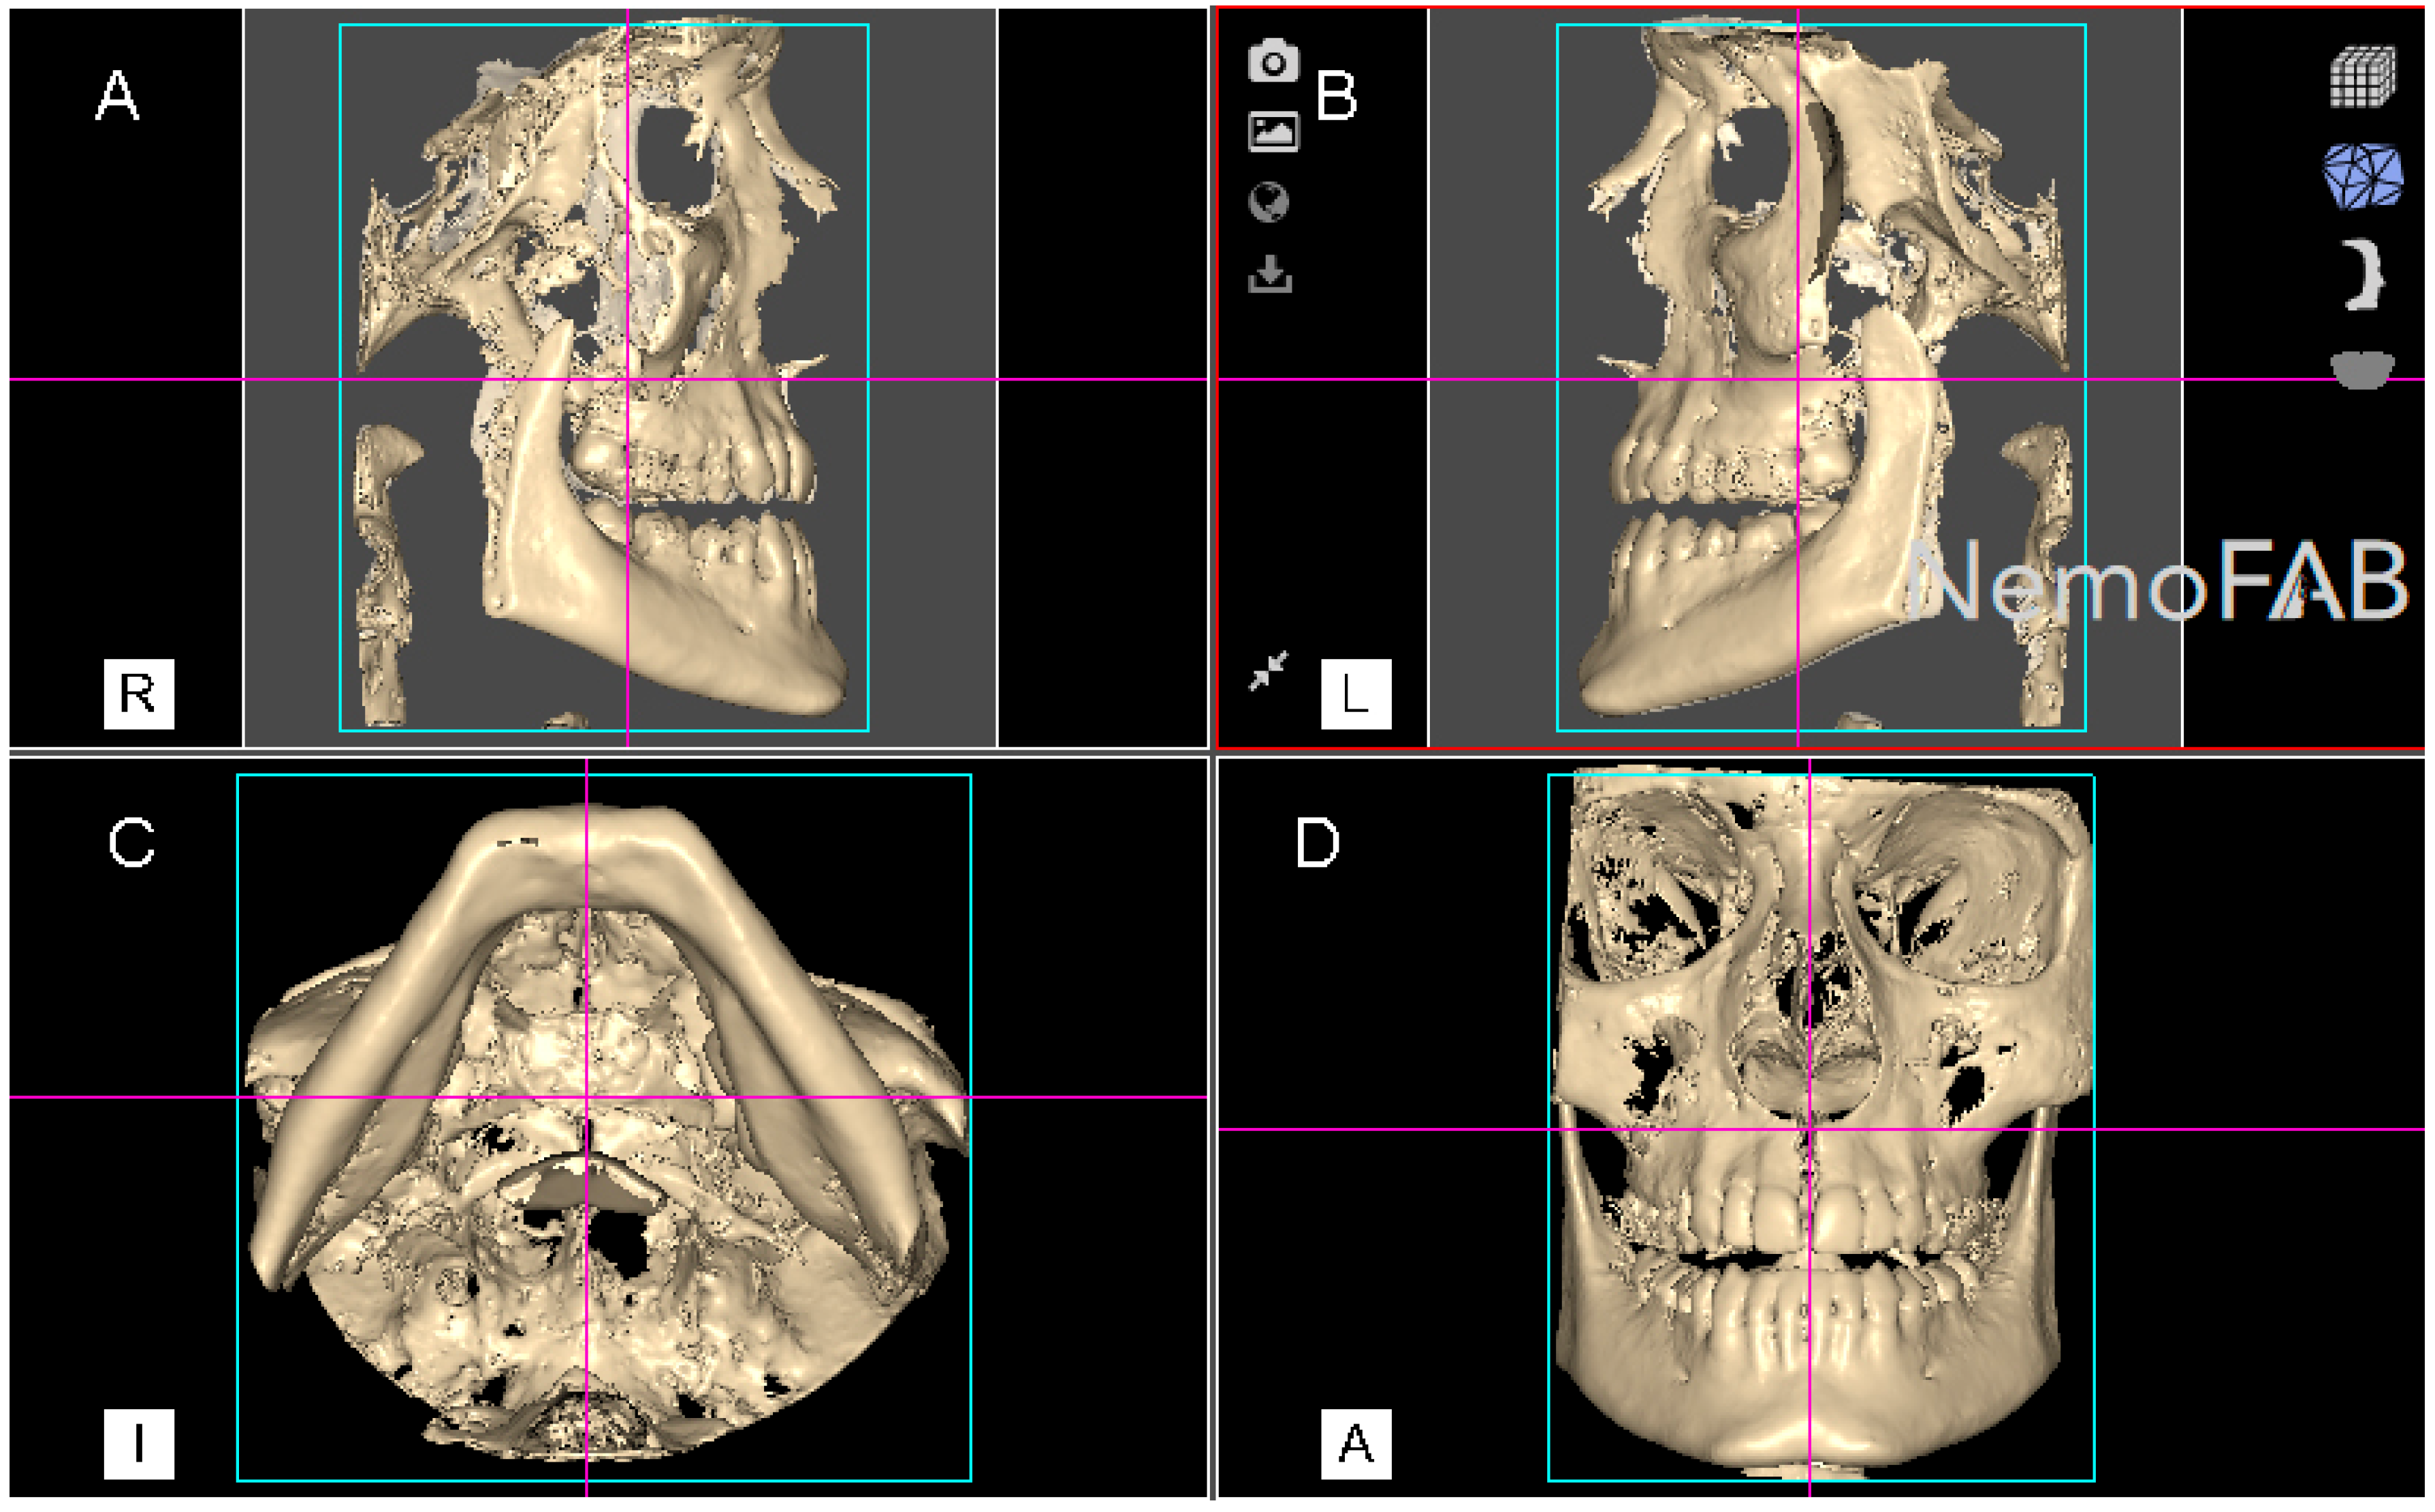

After the palatine suture expansion was achieved by rapid maxillary expansion appliances through disjunctor, all the patients were submitted to a postoperative CBCT scan (WhiteFox, Satelec, Merignac, France) with the following exposure parameters: 105.0 kV peak, 8.0 mA, 7.20 s, and a field of view of 15 mm × 13 mm. The position of the patient’s head was standardized so that the Frankfort plane was parallel, and the midsagittal plane was perpendicular to the ground. Afterwards, datasets from the postoperative CBCT scans (WhiteFox, Satelec, Merignac, France) were uploaded into the three-dimensional orthodontic-planning software (NemoFAB 3D NemoStudio® 19.2.0 uv 89 2KT, Nemotec; Madrid, Spain) to perform the volumetric measurement of the palatine suture expansion. Subsequently, the midpalatal suture was aligned to the sagittal axis and the palatal plane was aligned to the axial axis (Figure 2).

Figure 2.

(A) Right lateral, (B) left lateral, (C) bottom and (D) frontal view of the postoperative cone-beam computed tomography (CBCT) scans, aligned to the Frankfort plane and the midsagittal plane was perpendicular to the ground.